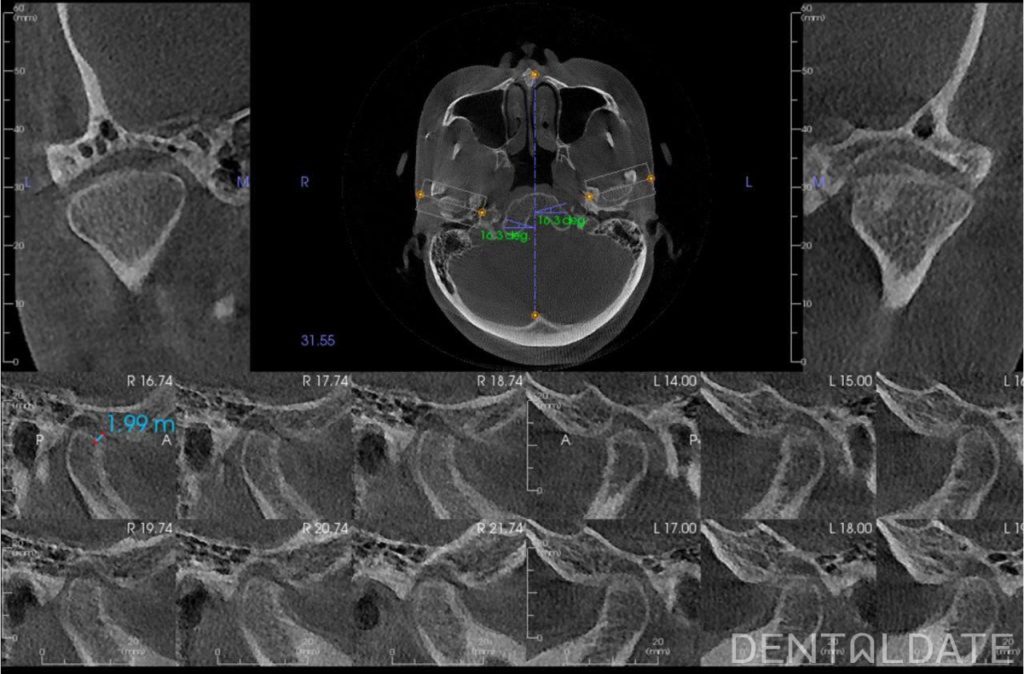

Complex treatment of TMJ arthrosis with orthodontic correction

In this clinical case, we want to demonstrate an approach focused on optimizing treatment timelines for temporomandibular joint (TMJ) osteoarthritis. The patient was diagnosed with TMJ osteoarthritis, confirmed by condylography and CT imaging.